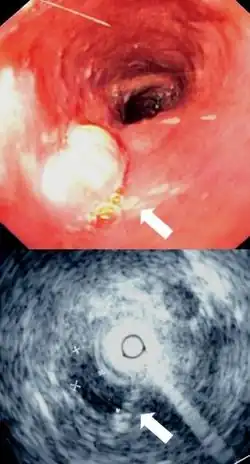

Although an occlusive tumor may be suspected on a barium swallow or barium meal, the diagnosis is best made with an examination using an endoscope. This involves the passing of a flexible tube with a light and camera down the esophagus and examining the wall, and is called an esophagogastroduodenoscopy. Biopsies taken of suspicious lesions are then examined histologically for signs of malignancy.

Additional testing is needed to assess how much the cancer has spread (see #Staging, below). Computed tomography (CT) of the chest, abdomen and pelvis can evaluate whether the cancer has spread to adjacent tissues or distant organs (especially liver and lymph nodes). The sensitivity of a CT scan is limited by its ability to detect masses (e.g. enlarged lymph nodes or involved organs) generally larger than 1 cm.[41][42] Positron emission tomography is also used to estimate the extent of the disease and is regarded as more precise than CT alone.[43] Esophageal endoscopic ultrasound can provide staging information regarding the level of tumor invasion, and possible spread to regional lymph nodes.

-

Endoscopic image of Barrett esophagus – a frequent precursor of esophageal adenocarcinoma -

Endoscopy and radial endoscopic ultrasound images of a submucosal tumor in the central portion of the esophagus -